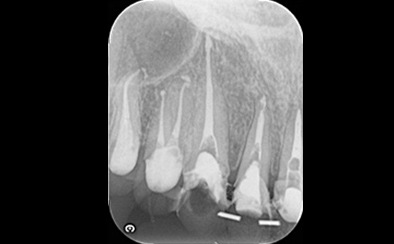

治療前

治療後

なるべく歯を残して、歯の神経も可能な限り保存し残していく方向で治療方法を検討しました。むし歯が大きく神経が侵されている歯は、抜髄を行い、精密根管治療の後にセラミックスクラウンを被せる治療方法を策定しました。患者さんのご希望と了解を得て治療を開始しました。

むし歯治療では、丁寧にむし歯だけを除去して健全な歯質だけを残します。名取歯科医院では、ラバーダムとマイクロスコープの使用が標準です。歯の根と神経の治療(根管治療)も行っていきます。

ラバーダムとはゴム製のシートで、治療する歯だけを露出させるように丁寧に切り取り、お口に装着します。唾液の中には天文学的な数の細菌が存在するため、一度治療した歯が再び悪化して再治療とならないためには、ラバーダムを装着し唾液や細菌に触れないように防湿を施した環境で治療することが何よりも大切で、歯科治療の基本です。歯の根元の黒い部分は膿の溜まった袋です。

むし歯が進行することで歯の神経まで細菌に侵されてしまった場合、昭和型の歯科治療では歯を抜いてしまう抜歯が当たり前でした。しかし、歯を抜いてしまうことで歯並びの乱れなど、ほかの歯への大きな影響があります。そこで自分の歯をできるだけ残すことを考えた「根管治療」や「保存治療」が選択されるようになってきました。

治療後の写真です。きちんと歯の根の治療(根管治療)を施すことで膿の袋も消失します。

歯ぐき(歯肉)の治療も大切です。歯ぐきを健康的な状態に治療していくことで、お口全体を審美的に優れた美しい状態に改善できます。このように歯ぐき(歯肉)の治療を行うことで、炎症を抑え、健康な状態をつくることができます。歯ぐきのコンディションを回復させると同時に、仮歯を入れます。しかしこれは治療中の隙間を埋めたり見た目を取り繕う「仮歯」とは異なります。プロビジョナルレストレーションと言い、最終的な歯(本歯)と同じ形体をもつ歯で、治療した歯や周囲の歯、反対側の歯、歯ぐきなどお口全体の回復と調和を整える大切な治療プロセスです。もちろんこの期間に仮歯での噛み合わせ、咀嚼や嚥下、または発音や発語など機能的な回復に不具合がないか、顎関節への影響や負担がないか検証する期間でもあります。

仮歯で機能回復の確認を行い、そしてさらに微調整を行います。機能的・審美的に改善を確認できた仮歯の形態を元にセラミックスクラウンを作製します。熟練した歯科技工士によるセラミックス制作を行い、装着後に最終的な微調整(咬合調整)を施し、むし歯治療、歯の根の神経治療(根管治療)、白いセラミックスによる修復治療のすべてが終了しました。

| 費用 | ジルコニアセラミック24本:5,280,000円 根管治療(小臼歯5本):770,000円 根管治療(前歯6本):792,000円 合計:6,842,000円 |

| リスク・副作用 | 治療中に一時的な咬合痛や冷温水痛、若干の歯肉の腫れ、発赤などを生じることがあります。また仮歯の時期には仮歯の脱離や破損の可能性、舌感などに違和感を覚えることがありますが、本歯に移行するまでに通常消失します。 ※すべて症例による違いや個人差があります。 |

※表示金額は全て税込みです。